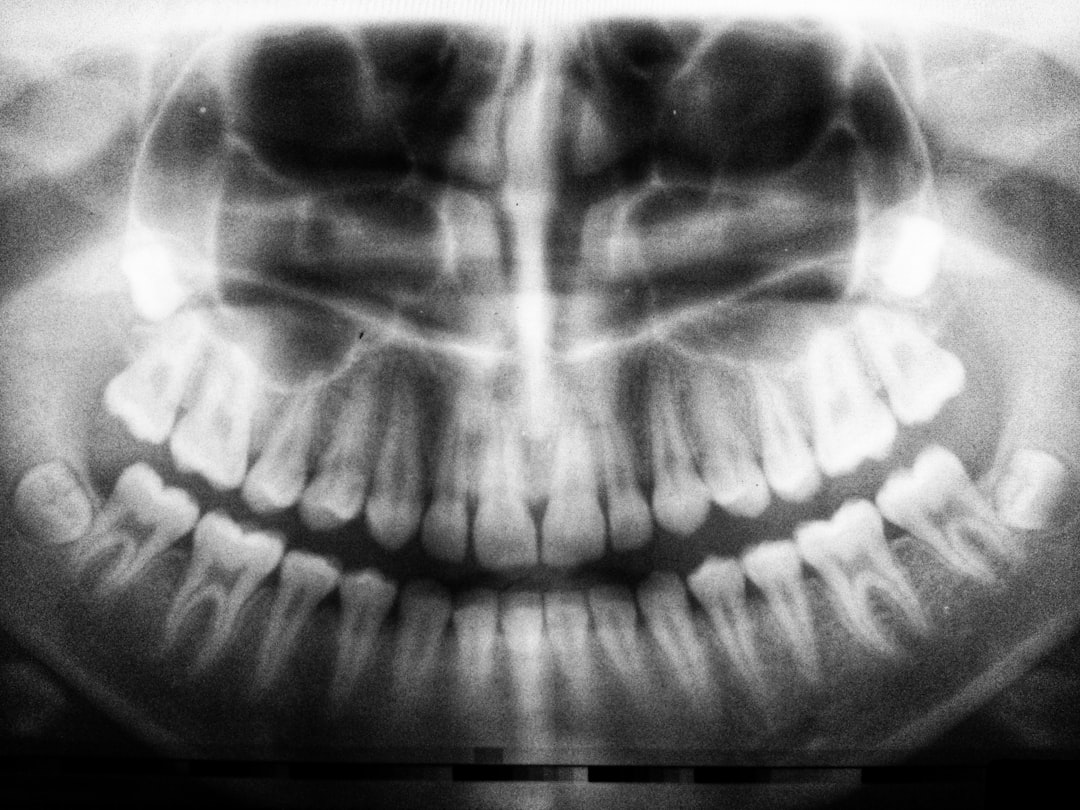

임플란트 시술에는 일반적으로 치아 뿌리 역할을 하는 티타늄 스크류를 식립하고, 뼈가 충분히 존재하지 않을 경우에는 뼈이식을 추가로 해야 합니다. 뼈이식의 경우, 사용되는 재료와 방법에 따라 비용이 달라지며, 제주 봉개동에서는 평균적으로 100만 원에서 300만 원가량 소요됩니다. 장기적으로 생각할 때, 이러한 비용은 결코 작은 금액이 아닙니다.

기본적으로 임플란트 시술에는 상담비, 진단비, 수술비, 그리고 보철비가 포함됩니다. 이러한 항목을 통해 평균적인 제주 봉개동 임플란트 뼈이식 비용 및 실손보험 가이드로서의 세부적인 구조를 이해할 수 있습니다. 구체적으로, 치료를 받기 전에는 다양한 의료기관에서 상담받고 비용과 치료 계획을 비교하는 것이 좋습니다.